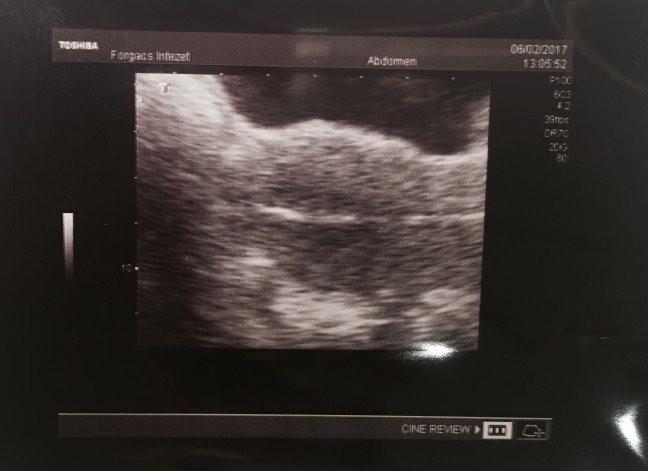

Embrió transzfer

Pénteken reggel jött a hívás a Forgács Intézetből, hogy a két életképes petesejtből mind a kettő megtermékenyült. 🙂 Kérték, hogy ma reggel 9 körül csörögjek, mert ha szépen növögetnek, akkor ma beültetik őket. Reggel már alíg vártam hogy 9 legyen, és csöröghessek. A Forgács Tanár Úrral beszéltem, aki elmondta, hogy mind a kettő szépen fejlődik, … Embrió transzfer részletei...